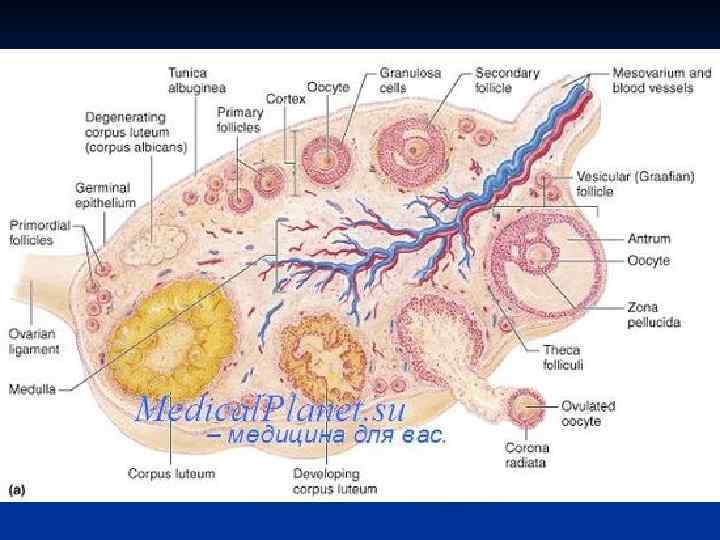

Женские половые органы, organa genitalia feminina

Женские половые органы, organa genitalia feminina